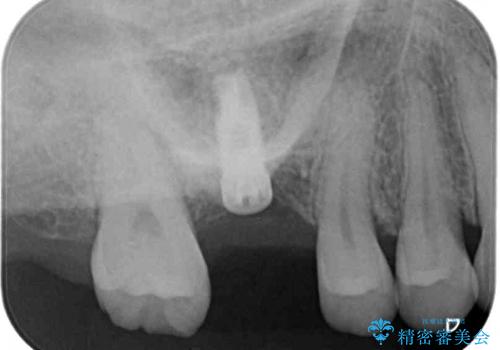

抜歯前のCTにより、インプラントを埋入するために必要な歯槽骨量が不足することが予想されたため、サイナスソケットリフトにより上顎洞内の粘膜を挙上して、インプラントを埋入することとしました。

虫歯を放置した期間が長かったため、対合の下顎大臼歯が上顎に迫ってきており、咬み合わせは非常にシビアでした。

仮歯装着中に頻繁に脱離したため、オールセラミッククラウンは脱離の少ないスクリュータイプとしました。